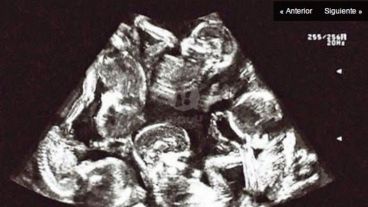

Mauricio calificó a su mujer Susana de “heroína” y contó que estuvieron 5 años intentando ser padres. “Se nos dio todo junto”, manifestó y recordó la mezcla de sorpresa y alegría que sintieron cuando en la primera ecografía pudieron ver “los 5 puntitos”.